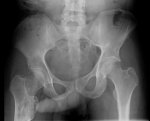

IMG20251208122511.jpg

Здравствуй двачик, сегодня мы с вами опять будем играть в рентгенолога, я вам буду постировать фоточки, а вы узнавать пиздецомы на них.

А пока мы обсуждаем этот сложный вопрос я вам фоочки буду показывать! Штош погнали!

IMG20251208145138.jpg

Где пиздецома?

>>327474983

Милиарный туберкулёз?

>>327475480

И опухоль тож, там рак желудка первичный